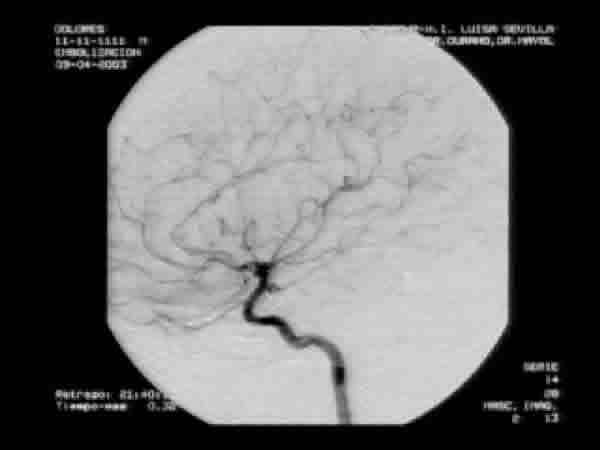

Solicitamos una angioRMC, informada como normal, y eco doppler de ambas órbitas en la que se nos informa de una mayor vascularización y mayor flujo demostrado con doppler color en la órbita izda. respecto de la derecha. La angio RMC con gadolinio (fig. 7) mostró unas imágenes que, sin ser concluyentes, sugerían la posibilidad de una fístula carótido-cavernosa izda. Al no estar plenamente convencidos de este diagnóstico decidimos, de acuerdo con el neurocirujano, practicar una arteriografía (fig. 8), la cual evidenció la existencia de un aneurisma en el territorio de la carótida izda. a la altura de la ACP. Dos días después se procedió a la embolización del aneurisma con espirales de platino (coils) (fig. 9).

Fig. 8.